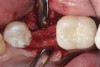

Fig 17. Bone graft was placed in the socket and a d-PTFE barrier was used to cover the graft. The bone graft material was placed beyond the alveolar housing to accommodate shrinkage of graft material and to facilitate attaining a wide alveolar ridge. The barrier was removed after 6 weeks.

Figure 17

Fig 18. Healed ridge exposed after 6 months.

Figure 18